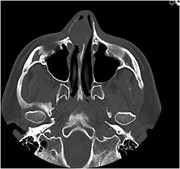

A surprising cause of unilateral nasal obstruction and epistaxis: nasal septal schwannoma

Brandon Cadd and others

Journal of Surgical Case Reports, Volume 2014, Issue 3, March 2014, rju023, https://doi.org/10.1093/jscr/rju023